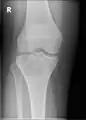

Typical and less common distribution of chondroblastomas

A variety of imaging studies can be used to diagnose chondroblastoma, with radiographs being the most common.[10][8] Laboratory studies are not considered useful.[14] Classical chondroblastoma (appearing on long bones) appears as a well-defined eccentric oval or round lytic lesion that usually involves the adjacent bone cortex without periosteal reaction.[10][13] A sclerotic margin can be seen in some cases.[10][13] For long bone chondroblastomas the tumor is typically contained to the epiphysis or apophysis but may extend through the epiphyseal plate.[10][13] Chondroblastomas are usually located in the medullary portion of bones and can, in some cases, include the metaphysis.[10][13] However, true metaphyseal chondroblastomas are rare and are typically the result of an extension from a neighboring epiphyseal legion.[10][13] Most lesions are less than 4 cm.[10] A mottled appearance on the radiograph is not atypical and indicates areas of calcification which is commonly associated with skeletally immature patients.[10] Additionally, one-third of all cases involve aneurysmal bone cysts which are thought to be the result of stress, trauma or hemorrhage.[10] In cases involving older patients or flat bones, typical radiographic presentation is not as common and may mimic aggressive processes.[10][13]

Other imaging techniques involve computed tomography (CT), magnetic resonance imaging (MRI), and bone scans, which may be helpful in determining the anatomical boundaries, associated edema, or biological activity of the chondroblastoma, respectively.[8][10] MRI studies may show extensive oedema around the lesion and show variable T2 signal intensity.[15]